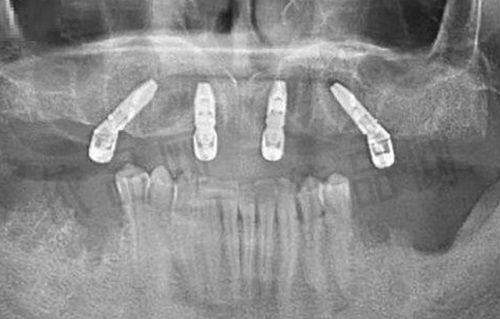

博恩口腔主推矫正和种植项目。该品牌在口腔行业深耕近30年,技术能力值得信赖。除了常规项目,像高难度的穿颧穿翼、全口即刻负重等治疗,它也具备相应的能力。